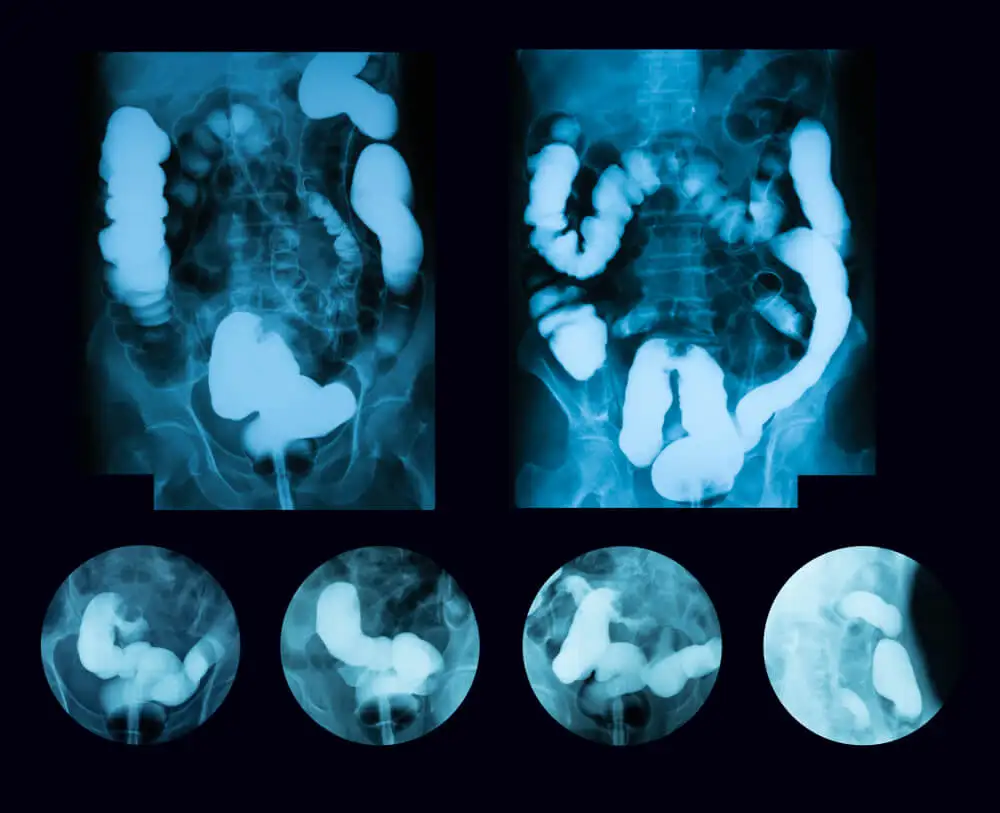

También auscultará la zona abdominal con el estetoscopio para escuchar los ruidos intestinales. Lo más probable es que ordene algunos exámenes para corroborar el diagnóstico, como los siguientes:

- Radiografía abdominal.

- Tomografía computarizada del abdomen.